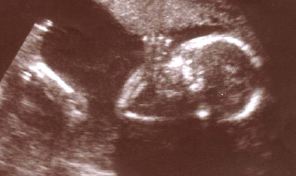

Jackie Deffenbaugh, our nurse practitioner, recording the baby's pulse (all you can see of Hua is the baby). Steve is holding the DAT machine. Photo courtesy of Dr. Lin Gu-Hui, Hua's mother.With Peak, I captured and edited two important samples for the piece. The first is a loop of our unborn baby's heartbeat, which we recorded with a Sony portable DAT machine at the doctor's office. (It was convenient, since the handheld Doppler machine they use to detect the pulse has a miniplug jack.)

Pulse Aria was inspired the first time my wife Hua and I heard the sound of our unborn baby's heartbeat, using a special Doppler detector at the doctor's office. Even though the baby was smaller than a pea, there was already a quick pulse. The sound was strange, like a vast ocean wave, but at the same time intimate and lonely--a tiny, indomitable spark.

Several months later, I sampled the heartbeat and used it as the foundation of a groove. Over the groove, the viola's rubato aria reflects the dark, earthy power and fragility of immanent life.